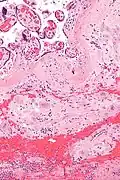

Micrograph of a chronic deciduitis, showing the characteristic plasma cells. H&E stain.

Chronic deciduitis is a type of long-lasting inflammation that arises in pregnancy and affects the endometrial stromal tissue (decidua).

It is associated with preterm labour.[1] The diagnosis rests primarily on the presence of plasma cells.[2]